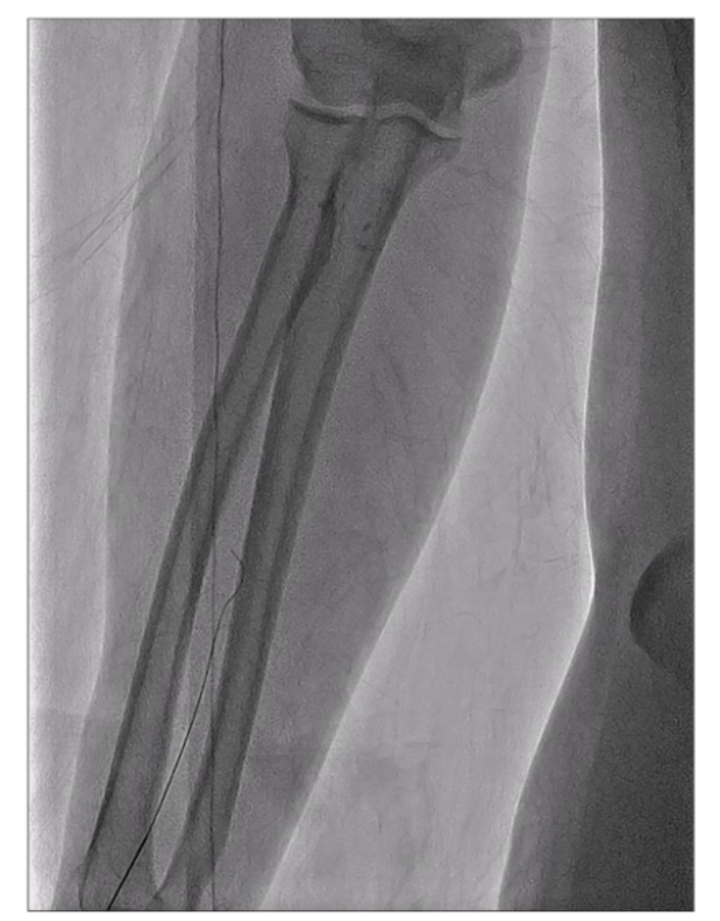

一般而言,桡动脉容易发生痉挛(见图1、图2),因此在确认鞘管放置成功后,立即向鞘管中注入抗痉挛药物混合液(通常由0.2毫升硝酸甘油和2.5毫克维拉帕米组成)以防止桡动脉痉挛。为了探讨肝素对桡动脉闭塞(RAO)发生率的影响,我们建立了两个组:肝素组,其中肝素(2500U)被添加到抗痉挛药物中;非肝素组,其中未添加肝素。

图1:x射线显示桡动脉痉挛(导丝穿过时阻力增加)